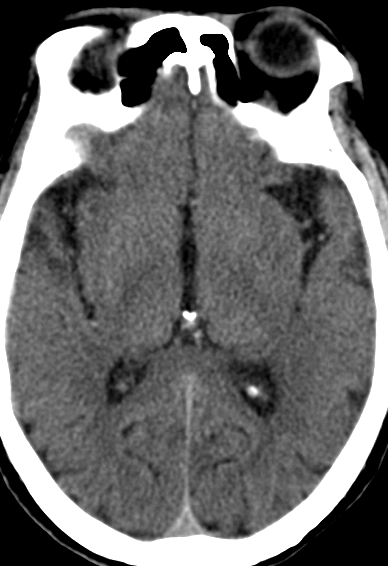

术后造影:

左侧颈内动脉C1段残余狭窄约10%,远端血管显影良好,前向血流mTICI 3级,未见远端血管栓塞及造影剂外渗。

动脉长鞘怎么置入【康德莱医械】经桡介入LA长鞘+Sim II通路组合处理颈内动脉狭窄_https://www.jmylbn.com_新闻资讯_第21张

动脉长鞘怎么置入【康德莱医械】经桡介入LA长鞘+Sim II通路组合处理颈内动脉狭窄_https://www.jmylbn.com_新闻资讯_第22张